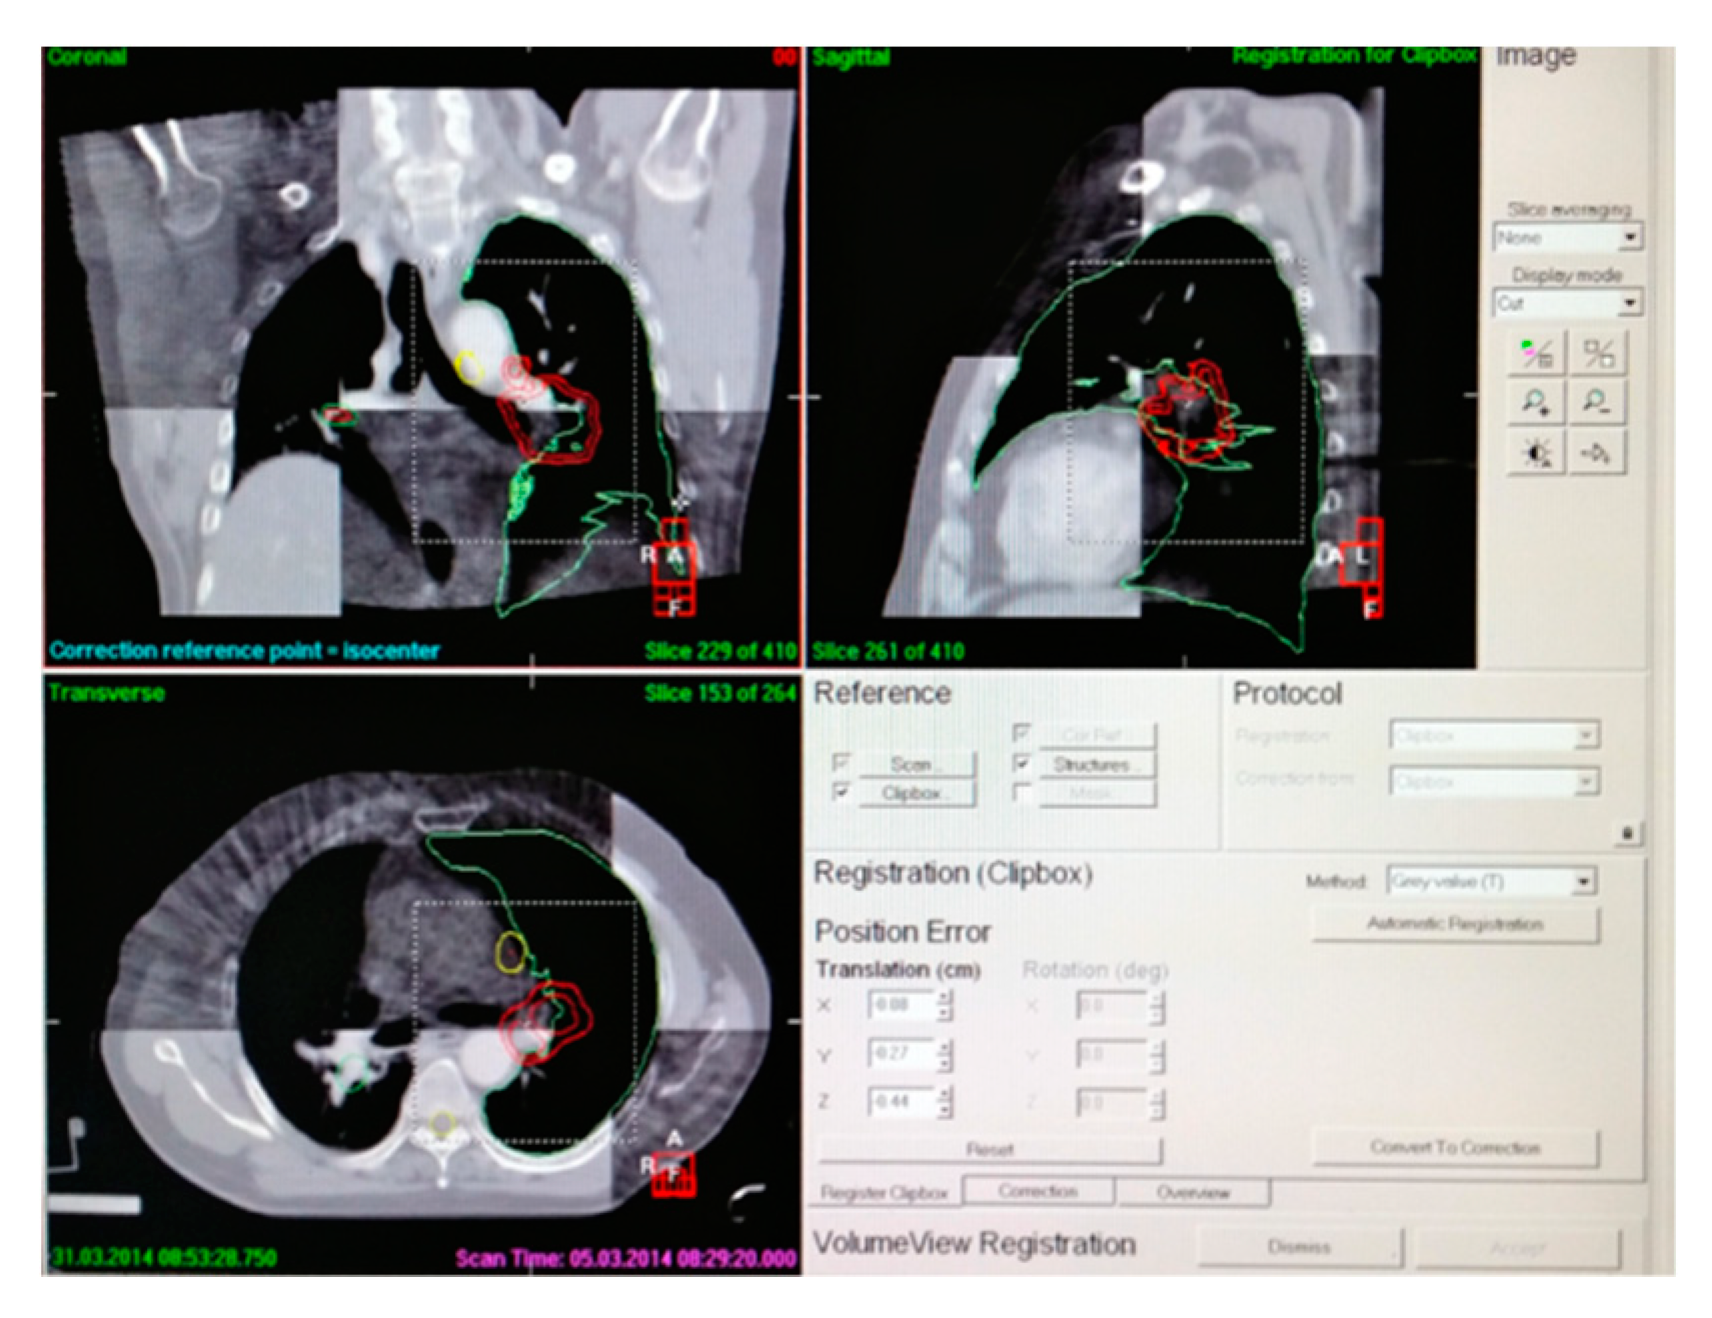

| Project | Group | Setup Error | Median | Maximum | Minimum | p Value |

|---|---|---|---|---|---|---|

| X (mm) | 1 | 0.81 ± 3.78 | 1.33 | 8.70 | −8.70 | 0.02 |

| 2 | −1.35 ± 0.45 | −0.30 | 3.20 | −1.90 | ||

| Y (mm) | 1 | 1.75 ± 4.55 | 2.15 | 10.00 | −8.75 | 0.01 |

| 2 | 1.15 ± 2.55 | 1.60 | 7.55 | −5.00 | ||

| Z (mm) | 1 | 2.45 ± 2.20 | 2.15 | 7.35 | −3.30 | 0.005 |

| 2 | 2.35 ± 0.35 | 1.25 | 5.00 | −2.75 | ||

| U (mm) | 1 | 0.60 ± 0.65 | 0.65 | 2.10 | −1.80 | 0.01 |

| 2 | 0.08 ± 0.32 | 0.00 | 0.65 | 0.70 | ||

| V (mm) | 1 | 0.35 ± 1.40 | 0.45 | 2.55 | −3.85 | 0.03 |

| 2 | −0.10 ± 0.50 | 0.00 | 1.30 | −2.00 | ||

| W (mm) | 1 | 0.45 ± 0.90 | 0.40 | 3.45 | −1.35 | 0.01 |

| 2 | 0.15 ± 0.32 | 0.08 | 1.25 | −1.25 |